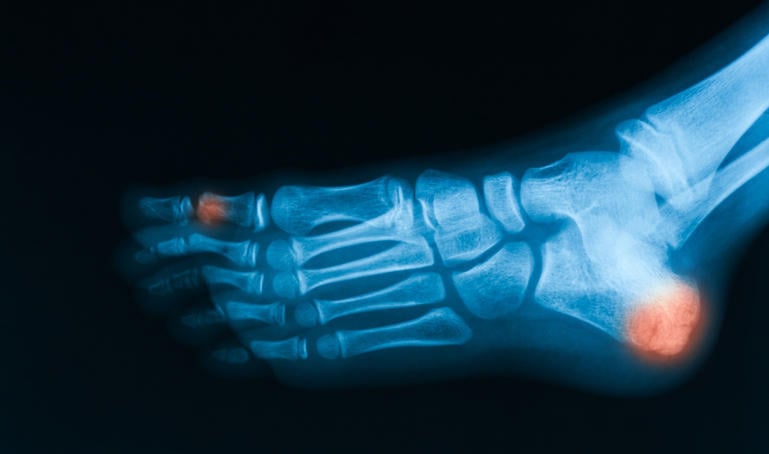

image radiographique de la vue oblique du pied, montrant une fracture du calcanéum et de l'orteil

La scintigraphie osseuse est une technique d’imagerie fonctionnelle utilisant la fixation d’un produit faiblement radioactif. Elle permet de rechercher des anomalies osseuses même minimes que les radiographies par exemple ne peuvent pas déceler. Mais comment se déroule un examen de scintigraphie osseuse ?

La scintigraphie osseuse est un examen particulier. En effet, avant de pratiquer les clichés du corps, le praticien injecte au patient un produit très peu radioactif qui a la particularité de se fixer aux os. L’appareil osseux est alors bien visible et il est plus facile de détecter de petites anomalies. La scintigraphie osseuse permet de détecter des problèmes osseux très précisément, comme des micro-fractures.

L’examen commence par l’injection intraveineuse d’un produit radioactif, dit ostéophile (qui "aime les os"). Il faut attendre environ 3 heures avant que le produit se fixe convenablement sur les os et que les clichés puissent être effectués. Le praticien procède alors à une série d’images du corps et particulièrement du pied et de la cheville grâce à une caméra rotative appelée gamma-caméra. La prise des clichés peut prendre 20 à 45 minutes. Une fois l’examen terminé, il faut boire abondamment afin d’évacuer le produit radioactif, car celui-ci s’évacue par les urines. L’examen se déroule donc sur environ 4 heures. Une fois l’examen terminé le travail peut être repris sans problème.